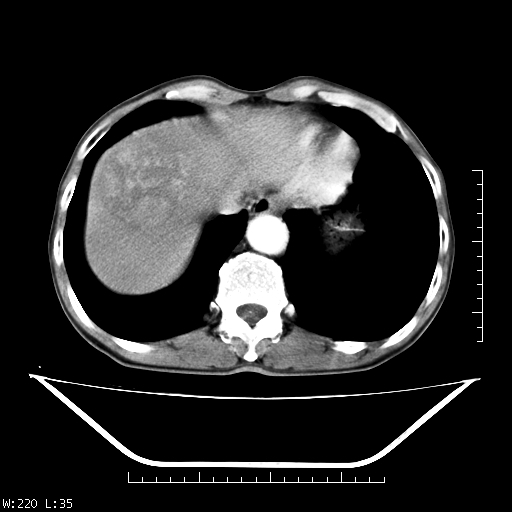

男,70,右上腹痛两月,有乙肝病史,b超提示肝占位,ct如下,请会诊。

肝右叶类圆型密度减低影,密度不均,边界清晰其内可见更低密度影,腹膜后可见小淋巴结肿大,增强扫描动脉期病灶明显强化,静脉期及延时扫描见强化不明显,快进快出表现。

平扫呈低密度占位,动脉期斑片状明显强化,病灶边缘清晰,见假包膜;门脉期呈低密度,符合肝癌快进快出强化特征

平扫呈低密度占位,动脉期斑片状明显强化,病灶边缘清晰,见假包膜;门脉期呈低密度,符合肝癌快进快出强化特征,可能为纤维板型。建议介入治疗,效果会很好的。